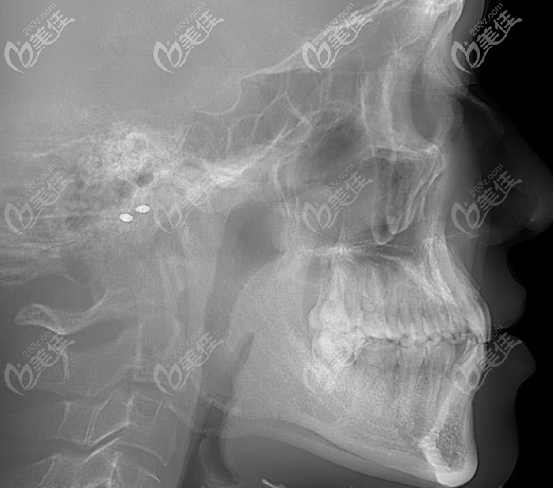

這是顱面的側(cè)位直面型照片,可以很明顯的看出有輕度的地包天現(xiàn)象。